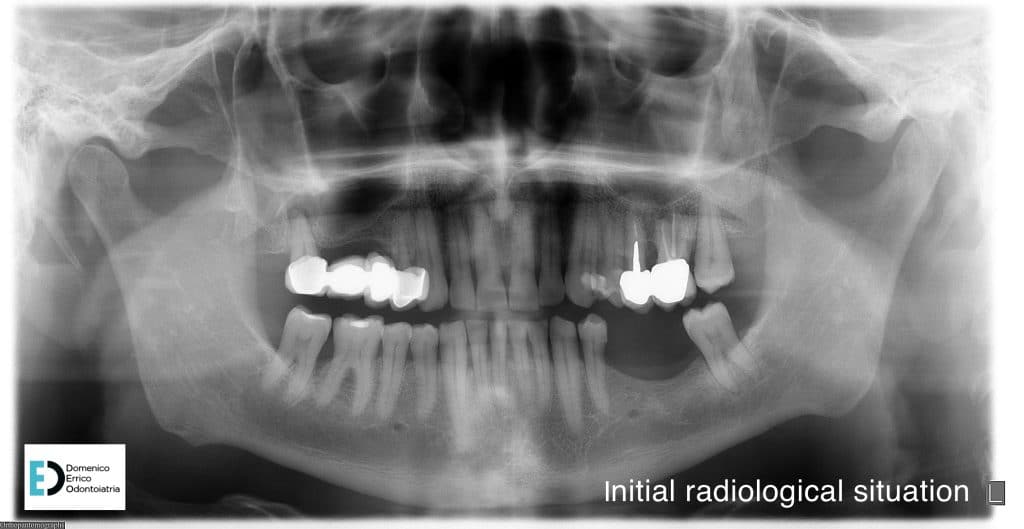

The 60-year-old patient comes to our attention too rehabilitate his oral function, because he is no longer able to chew on the left side. The patient presents with partial edentulism (missing teeth 35 and 36) dated, leading to resorption of the mandibular ridge and consequently, extrusion of opposing elements, which are fitted with an old prosthesis.

The treatment objectives are primarily functional: the restoration of volumes, necessary for implant rehabilitation due to insufficient bone height for fixture placement applying a mesh with a filler, consisting of 50% autologous bone and 50% heterologous bone; the reinstatement of chewing function by a second intervention to remove the mesh and simultaneously place two implant fixtures, concurrent with an increase of adherent gingival tissue level; and finally, the goal is to achieve the correct vertical relationship between the upper and lower arches through prosthetic rehabilitation of the upper arch with the replacement of the old prosthetic device.